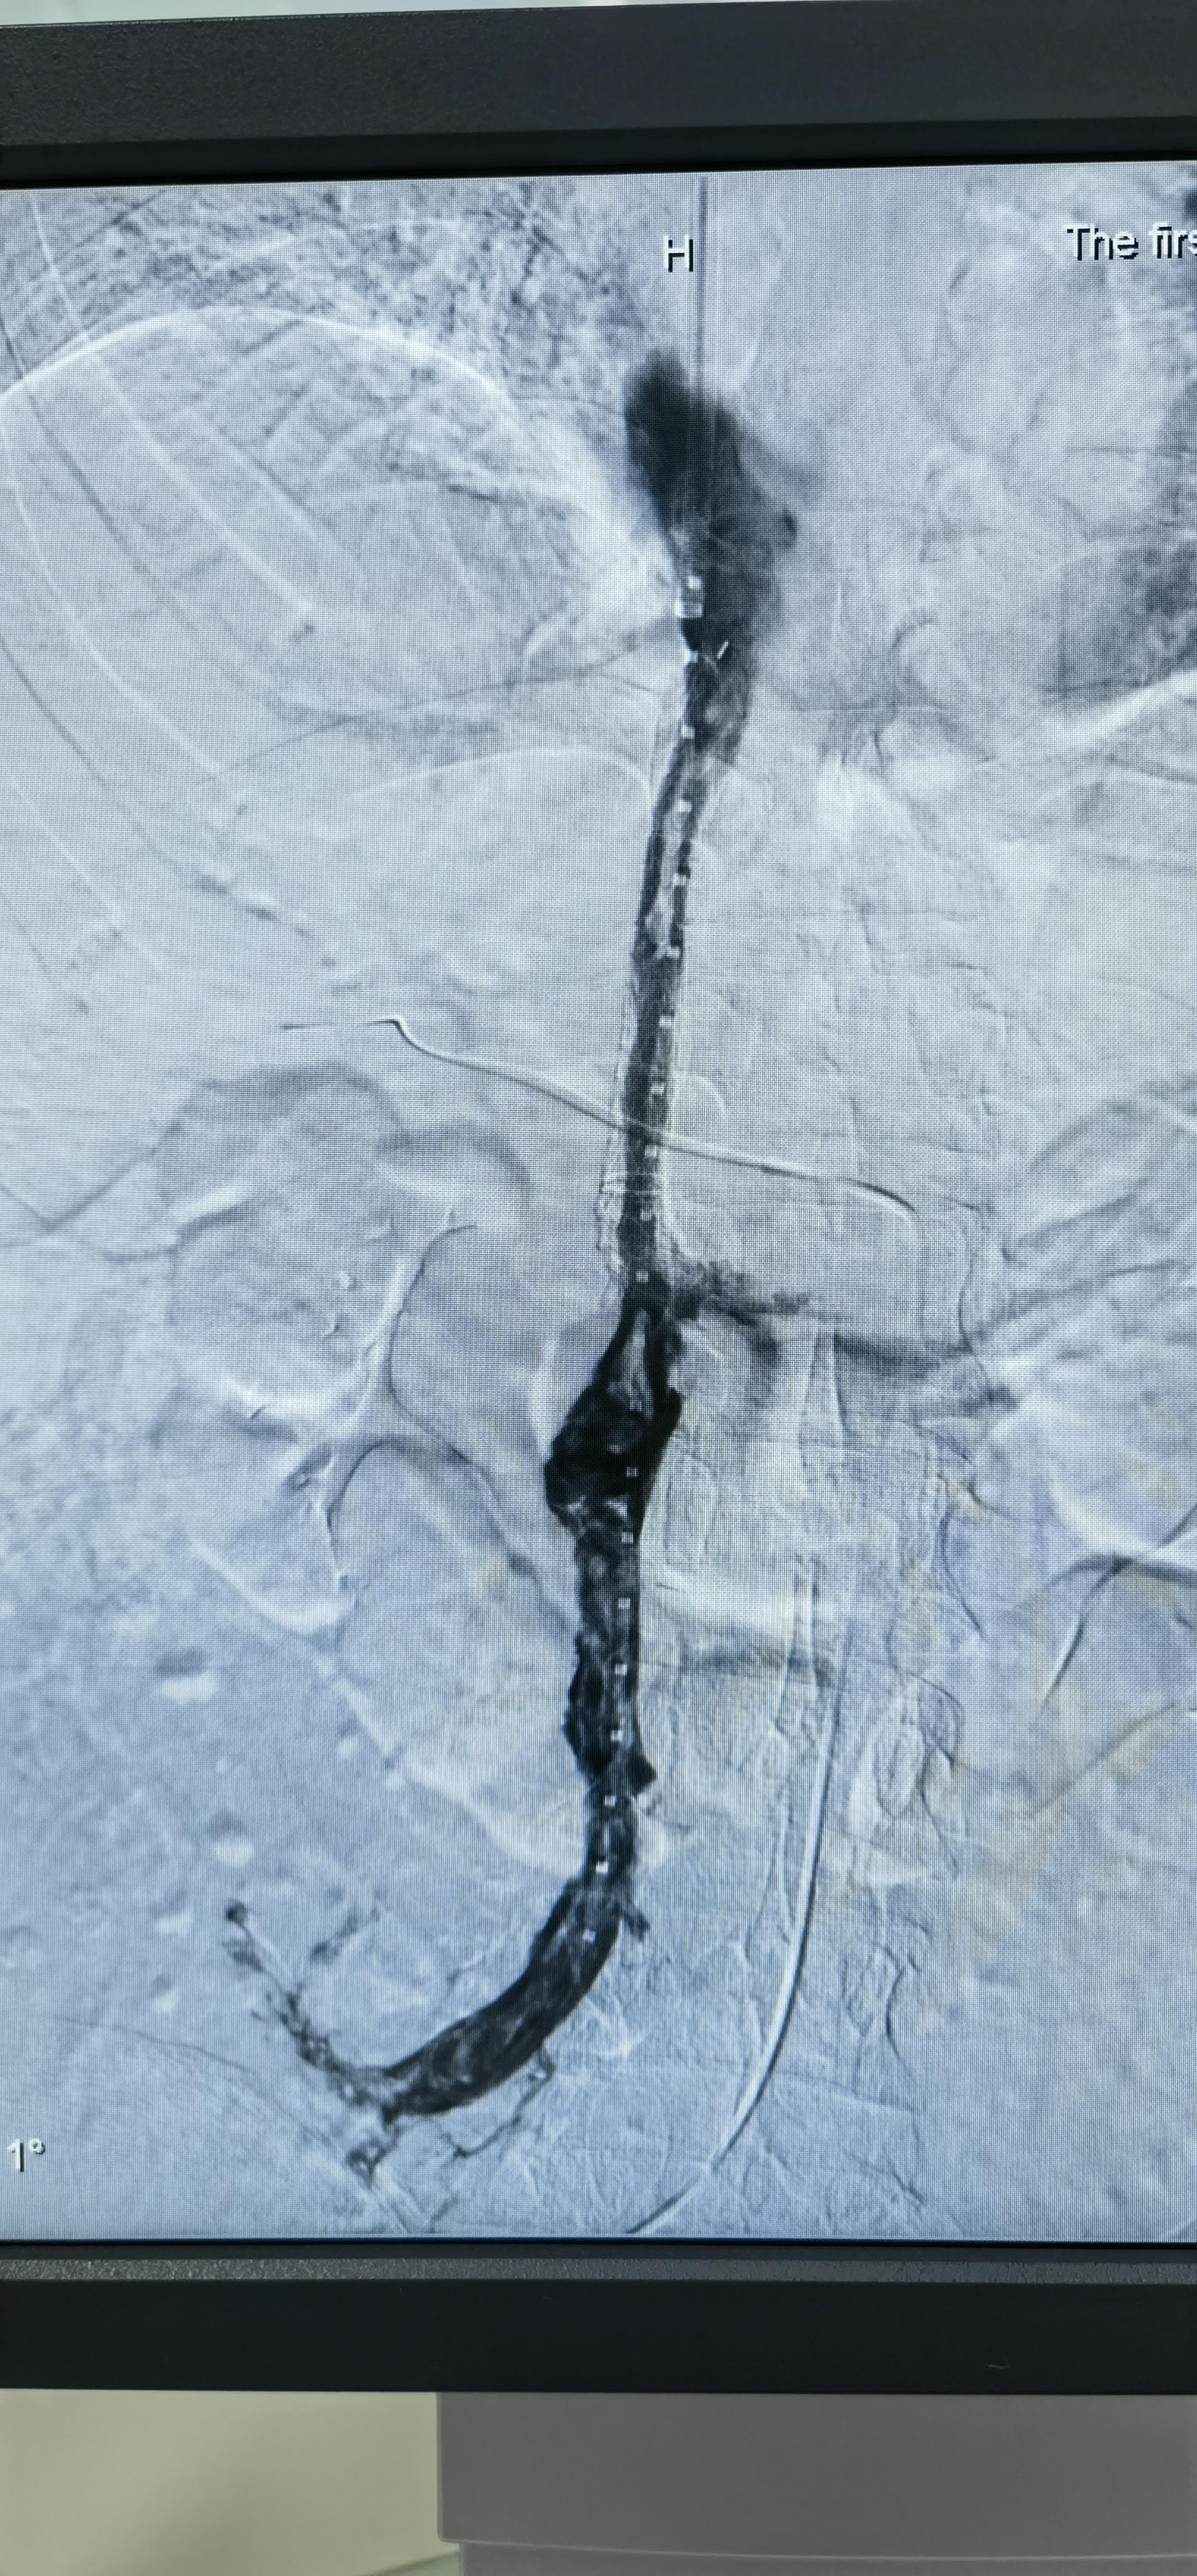

tips手术成功治愈门静脉及肠系膜静脉全程血栓患者【山东建筑材料网络

图片尺寸776x636

tipss治疗门静脉系统血栓一例 - 美篇

图片尺寸1537x2050